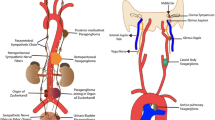

14.2 Tumor Origin

PHEOs and sympathetic-associated paragangliomas (symp-PGLs) develop from cells of the adrenal medulla or extra-adrenal chromaffin cells, respectively.

Chromaffin cells and sympathetic neurons derive from a common sympathoadrenal (SA) progenitor cell of neural crest origin. SA progenitor cells aggregate at the dorsal aorta, where they acquire a catecholaminergic neural fate. Subsequently, the cells migrate ventrally to invade the fetal adrenal cortex and form the adrenal medulla, as well as dorsolaterally to form sympathetic ganglia. Most extra-adrenal chromaffin cells regress via apoptosis. The organ of Zuckerkandl (OZ) constitutes the largest chromaffin paraganglia in the embryo and regresses after birth via autophagy [11]. Adrenal medulla and persistent extra-adrenal chromaffin cells located in the retroperitoneum and posterior mediastinum represent the chromaffin paraganglia system in adults. These cells possess the machineries to synthesize, store, release, and take up catecholamines, including the enzymes for noradrenaline synthesis. They have been named “chromaffin” by Kohn (1902) because of their characteristic staining property by chromium salts [12]. These embryological bases explain why PHEO and symp-PGL can be widely distributed along the sympathetic nervous system in the posterior mediastinum and retroperitoneum. In contrast, HNPGLs are derived from neural crest cells of the parasympathetic nervous system, with only 20 % producing and/or secreting catecholamines, usually dopamine or its metabolite 3-methoxytyramine [13–15]. Furthermore, these tumors are usually benign, except those caused by succinate dehydrogenase subunit B (SDHB) gene mutations, which are considered aggressive either locally or by the development of metastatic disease [5, 16–18].